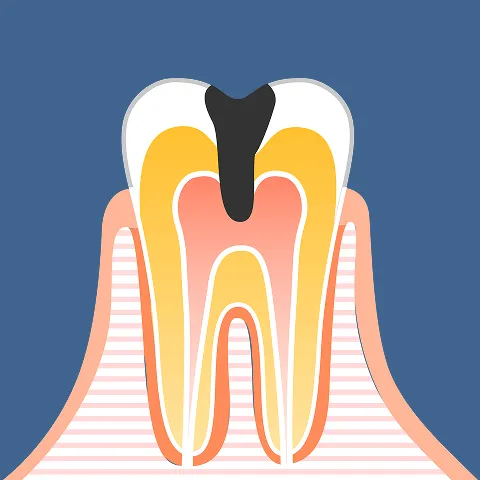

01歯の寿命を決める「生命線」

それが歯髄(神経)歯の内部には、「根管(こんかん)」と呼ばれる細い管が通っており、その中には「歯髄」という組織が満たされています。 歯髄は単なる痛みを感じるセンサーではありません。血管を通じて歯の内側から水分や栄養を供給し、歯を硬く丈夫に保つための「心臓部」とも言える極めて重要な器官です。 この歯髄が健全である限り、歯は弾力性を保ち、噛む力に耐え続けることができます。

02感染の恐怖

放置すれば「骨」まで溶かす虫歯が重症化し、細菌がこの「歯髄」にまで到達すると、事態は一刻を争います。 細菌に侵された歯髄は激しく炎症を起こし(歯髄炎)、耐え難い痛みや顔面の腫れを引き起こします。 恐ろしいのは、一度感染した歯髄は自然治癒することなく壊死し、腐敗していくという事実です。 放置すれば、細菌は根の先から顎の骨へと侵入し、骨を溶かしながら膿の袋(根尖病巣)を作ります。こうなると、最悪の場合は抜歯を避けられなくなります。

03根管治療とは、「歯の救命措置」

汚染された歯髄や細菌を徹底的に除去・消毒し、再び歯として機能させるための治療。それが「根管治療(歯内療法)」です。 しかし、複雑に入り組んだ根管内を肉眼だけで完璧に清掃することは不可能です。 だからこそ当院では、マイクロスコープやラバーダム防湿といった世界水準の設備を完備し、細菌を「見逃さない」「入れない」精密治療によって、かけがえのない天然歯を抜歯の危機から救い出します。

虫歯の進行ステージと治療の分岐点

虫歯の進行度は、医学的に「C1」から「C4」の4段階に分類されます。

初期段階であれば簡単な処置で済みますが、細菌が歯の内部にある「神経(歯髄)」に到達した瞬間から、治療の難易度と重要性は劇的に高まります。

- C1

エナメル質の溶解

(要観察・初期治療) - C2

象牙質の汚染

(修復治療) - C3

歯髄炎

(神経への感染) - C4

歯質崩壊・残根

(保存の限界・

抜歯の危機)

「C3・C4」は、歯を失う直前の危険信号。 未来を変えるのは、感染源を断つ「精密根管治療」です。